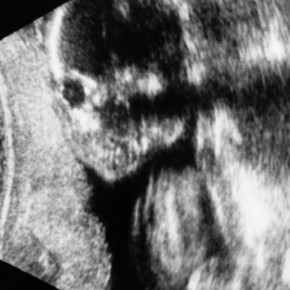

妻の腹の中にいるア・イ・ツ。 どうやら我が子の性別が判明した模様です。 https://naotokimura.tokyo/archives/12439 どうやら「男児」である事が判明した模様。 今だから言えるのですが、 […]